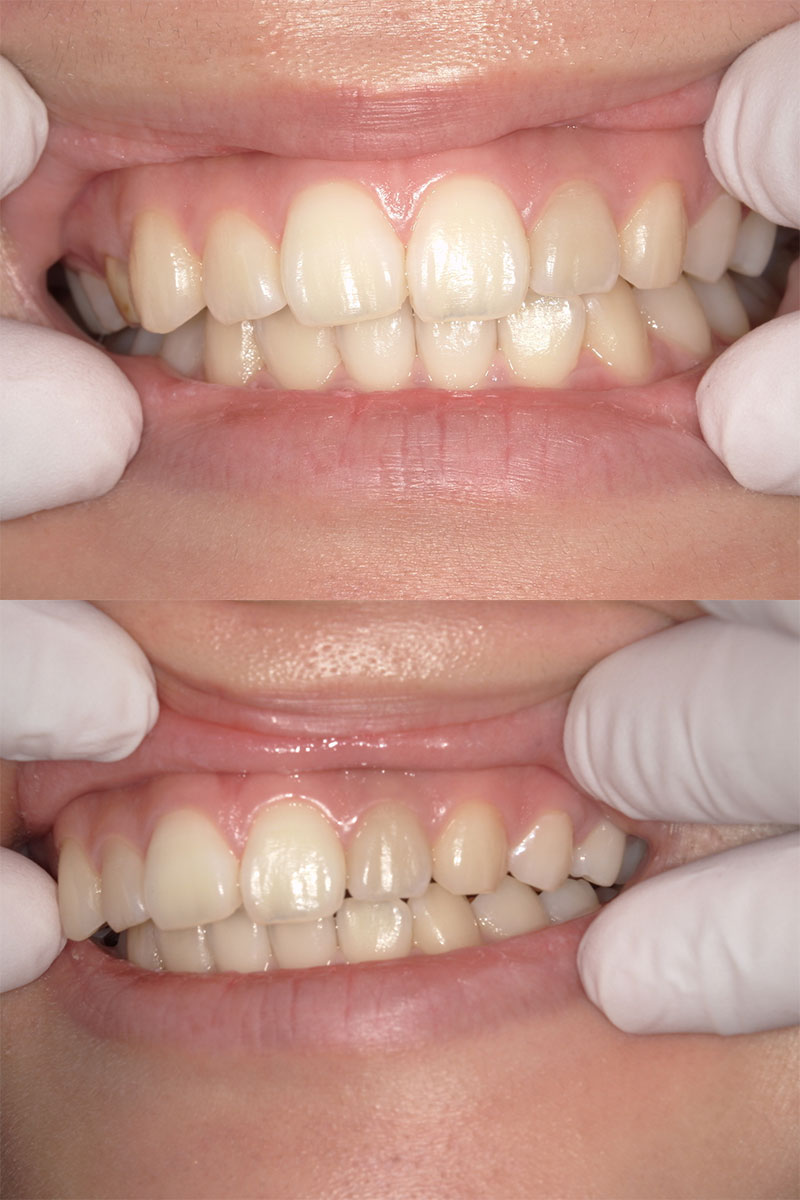

ワイヤー矯正+インプラント症例

治療前

Before

治療後

After

年齢 43歳

性別 女性

主訴 左下の乳歯を抜きたい